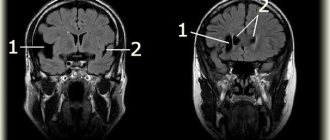

As we have already mentioned, leukoaraiosis is visible on CT and MRI neuroimages of the brain , with a decreased and increased frequency, respectively. MRI of the brain , including T2 and FLAIR series, is the most common technique for detecting leukoaraiosis. The Fazekas grading scale (Fig. 3) is most often used to determine the degree of white matter lesions on MRI images: – grade 0 : no lesions; – grade 1 : isolated lesions; – degree 2 : lesions are connected to each other; – grade 3 : lesions covering specific areas of the brain.

Fig. 3 Fazekas rating scale.